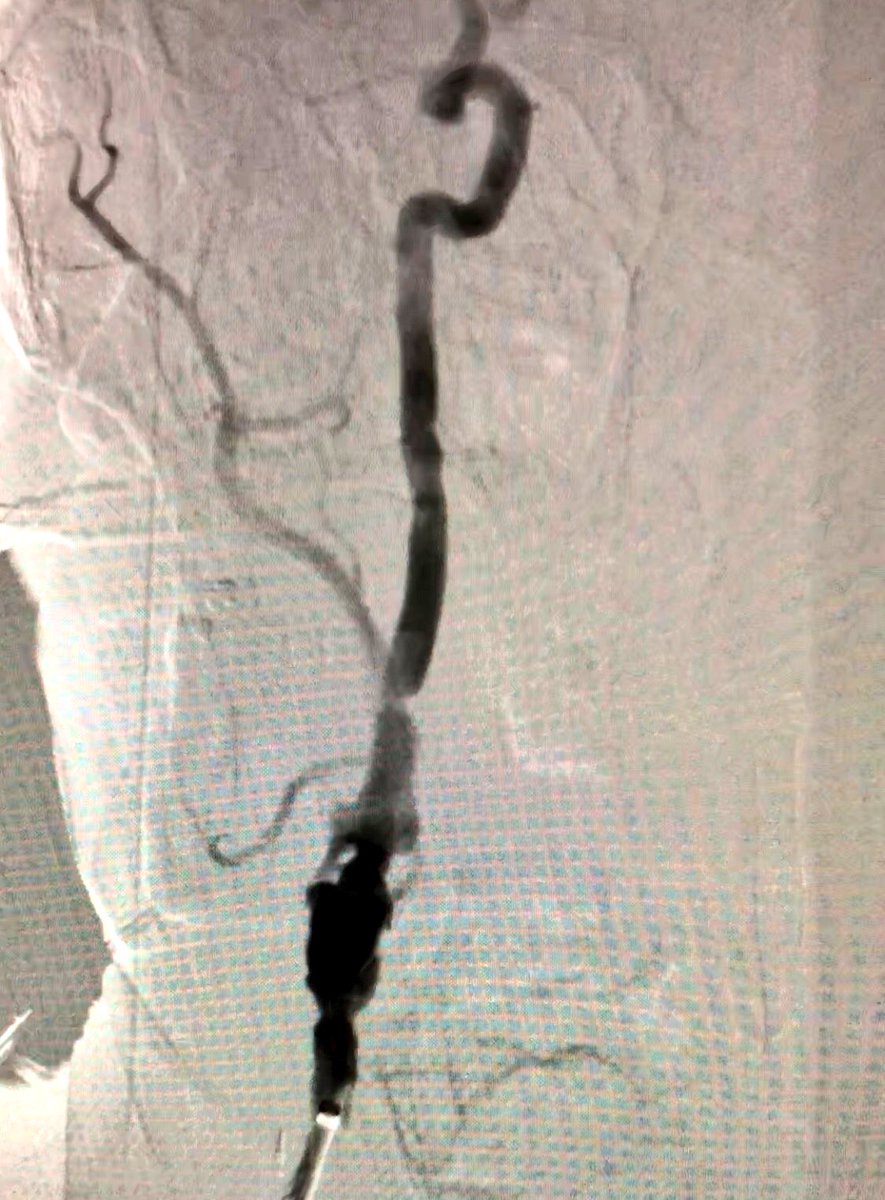

56 y/o WM with symptomatic R CCA/ICA disease, previous CEA. Carotid artery stenting planned via #RadialFirst approach but converted to ulnar based on vessel size by ultrasound #SCAIPAD